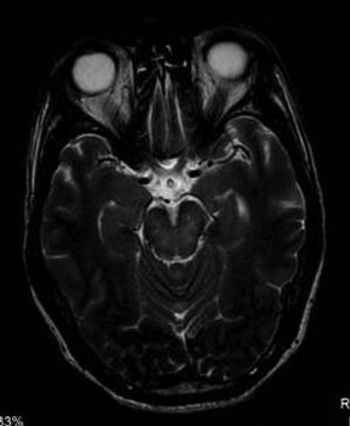

Case History: Patient presented with vision difficulty for one year, which increased in severity over last two months.